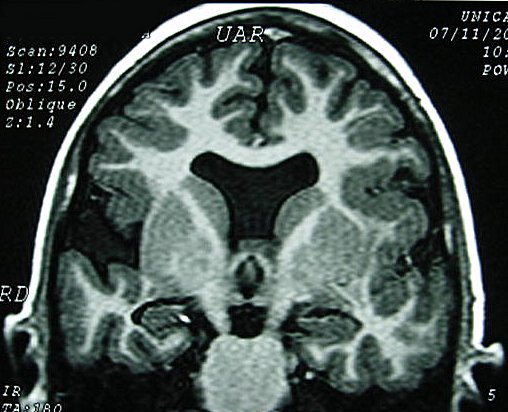

ГМ. Шизэнцефалия. +

Шизэнцефалия характеризуется расщеплением коры головного мозга линеинои формы, которое распространяется от желудочков к субарахноидальному пространству. Предположительно возникновение шизэнцефалии связано с окклюзией средних мозговых артерий, что может объяснить двусторонний характер поражения. В случаях шизэнцефалии нарушение сосудистого питания приводит не столько к разрушению мозговой ткани, сколько к ее неправильному формированию. Сочетание шизэнцефалии с другими аномалиями развития мозга свидетельствует о наличии другого механизма ее возникновения - первичных нарушений в большая часть коры разрушается. Многие из выживших детей страдают тяжелой умственной отсталостью.

Основным диагностическим критерием шизэнцефалии является наличие двусторонних дефектов, исходящих из боковых желудочков в направлении к наружной поверхности коры головного мозга. Обычно дефекты располагаются симметрично, хотя могут быть и односторонними.